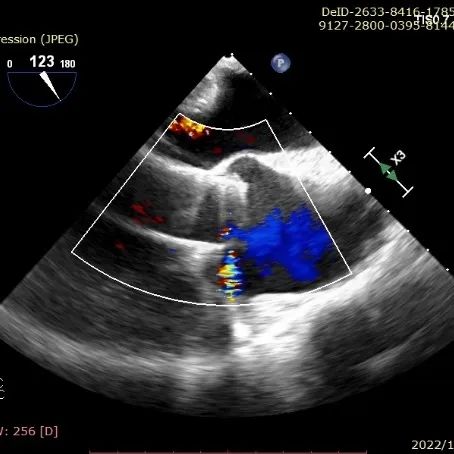

6. CDFI:主动脉半口舒张期可见大量反流信号。

TEE示主动脉瓣大量反流